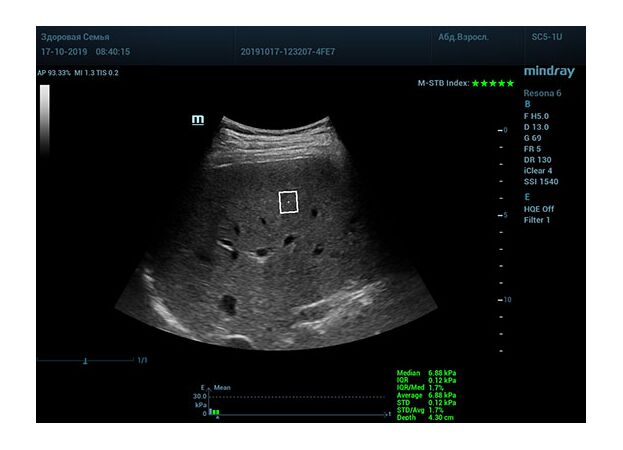

Определение плотности печени. Не ошибся ли оператор при измерении эластических свойств печени? Для оценки критериев качества предусмотрен индекс MBT, который покажет насколько «твердой» была рука оператора и двигалась ли печень. При MBT 5* рука тверда и показатели достоверны. Для оценки качества результатов используется IQR индекс, отображающий колебания показателей в точке измерения при расчете медианы. Показатели при IQR <30% считаются приемлемыми. Техника сканирования через межреберные промежутки требует размещение окна интереса на несколько сантиметром ниже капсулы, для исключения эффекта реверберации. Установка ROI на паренхиму без захвата сосудов, для исключения погрешностей измерения.

Стадия фиброза определяется по системе METAVIR Staging, построенной на данных биопсии и сопоставлении с данными эластографии. Своевременная диагностика фиброза, и начало его лечения, залог благоприятного исхода заболевания.